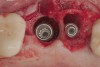

The challenge in removing implants fractured at the connection is primarily the difficulty in using reverse torque instrumentation. This method involves engaging the internal aspect of the implant to be removed. With a fractured implant, this method may cause further fracture, complicating its removal. Most commonly, these implants are removed with hollow, trephine drills. For a trephine to be effective, the inner diameter must be slightly larger than the widest portion of the fractured implant. This ensures that the trephine can move along the entire length of the implant without cutting into it. If the implant is sectioned at it's widest portion, which unfortunately results in significant spreading of titanium debris, a narrower trephine can be utilized to help conserve additional bone. After the threads of the implant body are no longer in contact with the surrounding bone, a small, root elevator is inserted circumferentially to fracture the apical portion of the fixture from the bone below. This is a very delicate procedure, especially when the implant is in close proximity to adjacent teeth or implants, the maxillary sinus, or the inferior alveolar canal. With proper diagnostics, which often include cone-beam computed tomography (CBCT) scans to evaluate the surrounding bone in three dimensions, this can be done safely. Figure 3 depicts an example of an implant that was removed using reverse torque instrumentation and one that was removed using a trephine.

(3.) Two implants removed with two separate techniques. The narrow implant had an abutment that was easily removed, making it possible to engage with a reverse torque device. The wider implant contained a fractured abutment screw and required removal with a trephine. Its wider platform dictated that the trephine fit over this portion, and the osseointegrated bone can be seen attached to the explanted fixture.

Figure 3